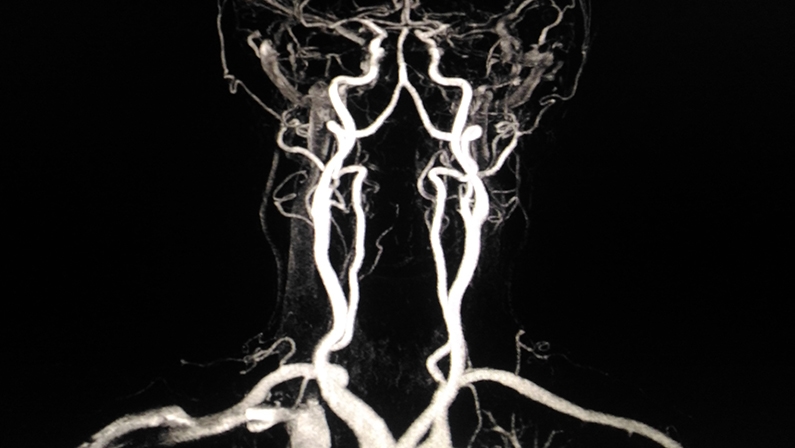

Magnetic resonance imaging (MRI) employs strong magnetic fields and radio waves to generate detailed images of soft tissues in the body.

While MRI is not the first-choice method for diagnosing blood clots, it can be valuable in certain situations, such as detecting clots in the deep veins of the pelvis.

MRI can offer excellent visualization of blood vessels and surrounding tissues, aiding in diagnosing and managing clot-related conditions.